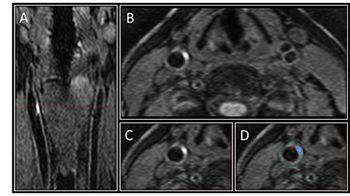

MRI finds possible marker for cardiovascular disease among asymptomatic diabetics.